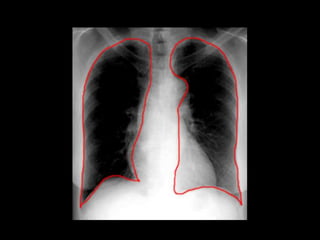

The document discusses the anatomy of the chest x-ray and CT scan by describing the lobes of the lungs and their locations. It also mentions the heart, mediastinum, hilum, and ribs. Several axial, coronal, and sagittal CT images are included with labels pointing out structures like the trachea, bronchi, lobes of the lungs, and fissures. In summary, the document provides an overview of lung and chest anatomy as seen on x-rays and CT scans through text descriptions and labeled medical images.